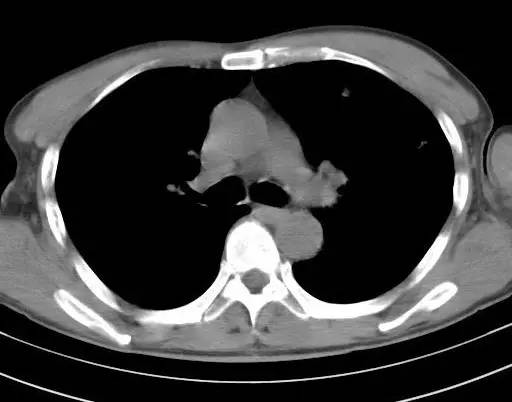

治疗前CT(图1-8):两肺胸膜下散在多发斑片状、结节状伴空洞影,边缘欠清晰。

治疗后十天CT(图9-12):双肺病灶明显缩小,有所吸收。